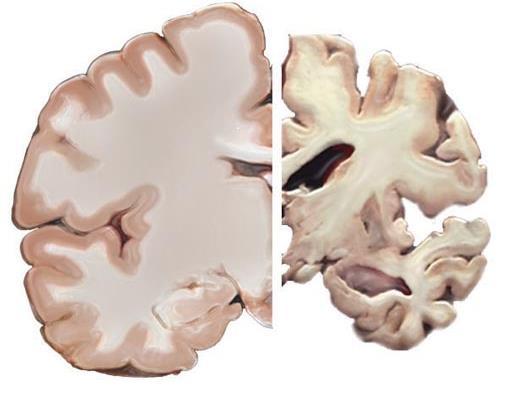

Dementia is the most common of the so-called neurodegenerative brain diseases (others include Parkinson’s disease and ALS/Lou Gehrig’s disease)

The most common type of dementia is Alzheimer’s disease

Dementia is the most common neurodegenerative brain disease